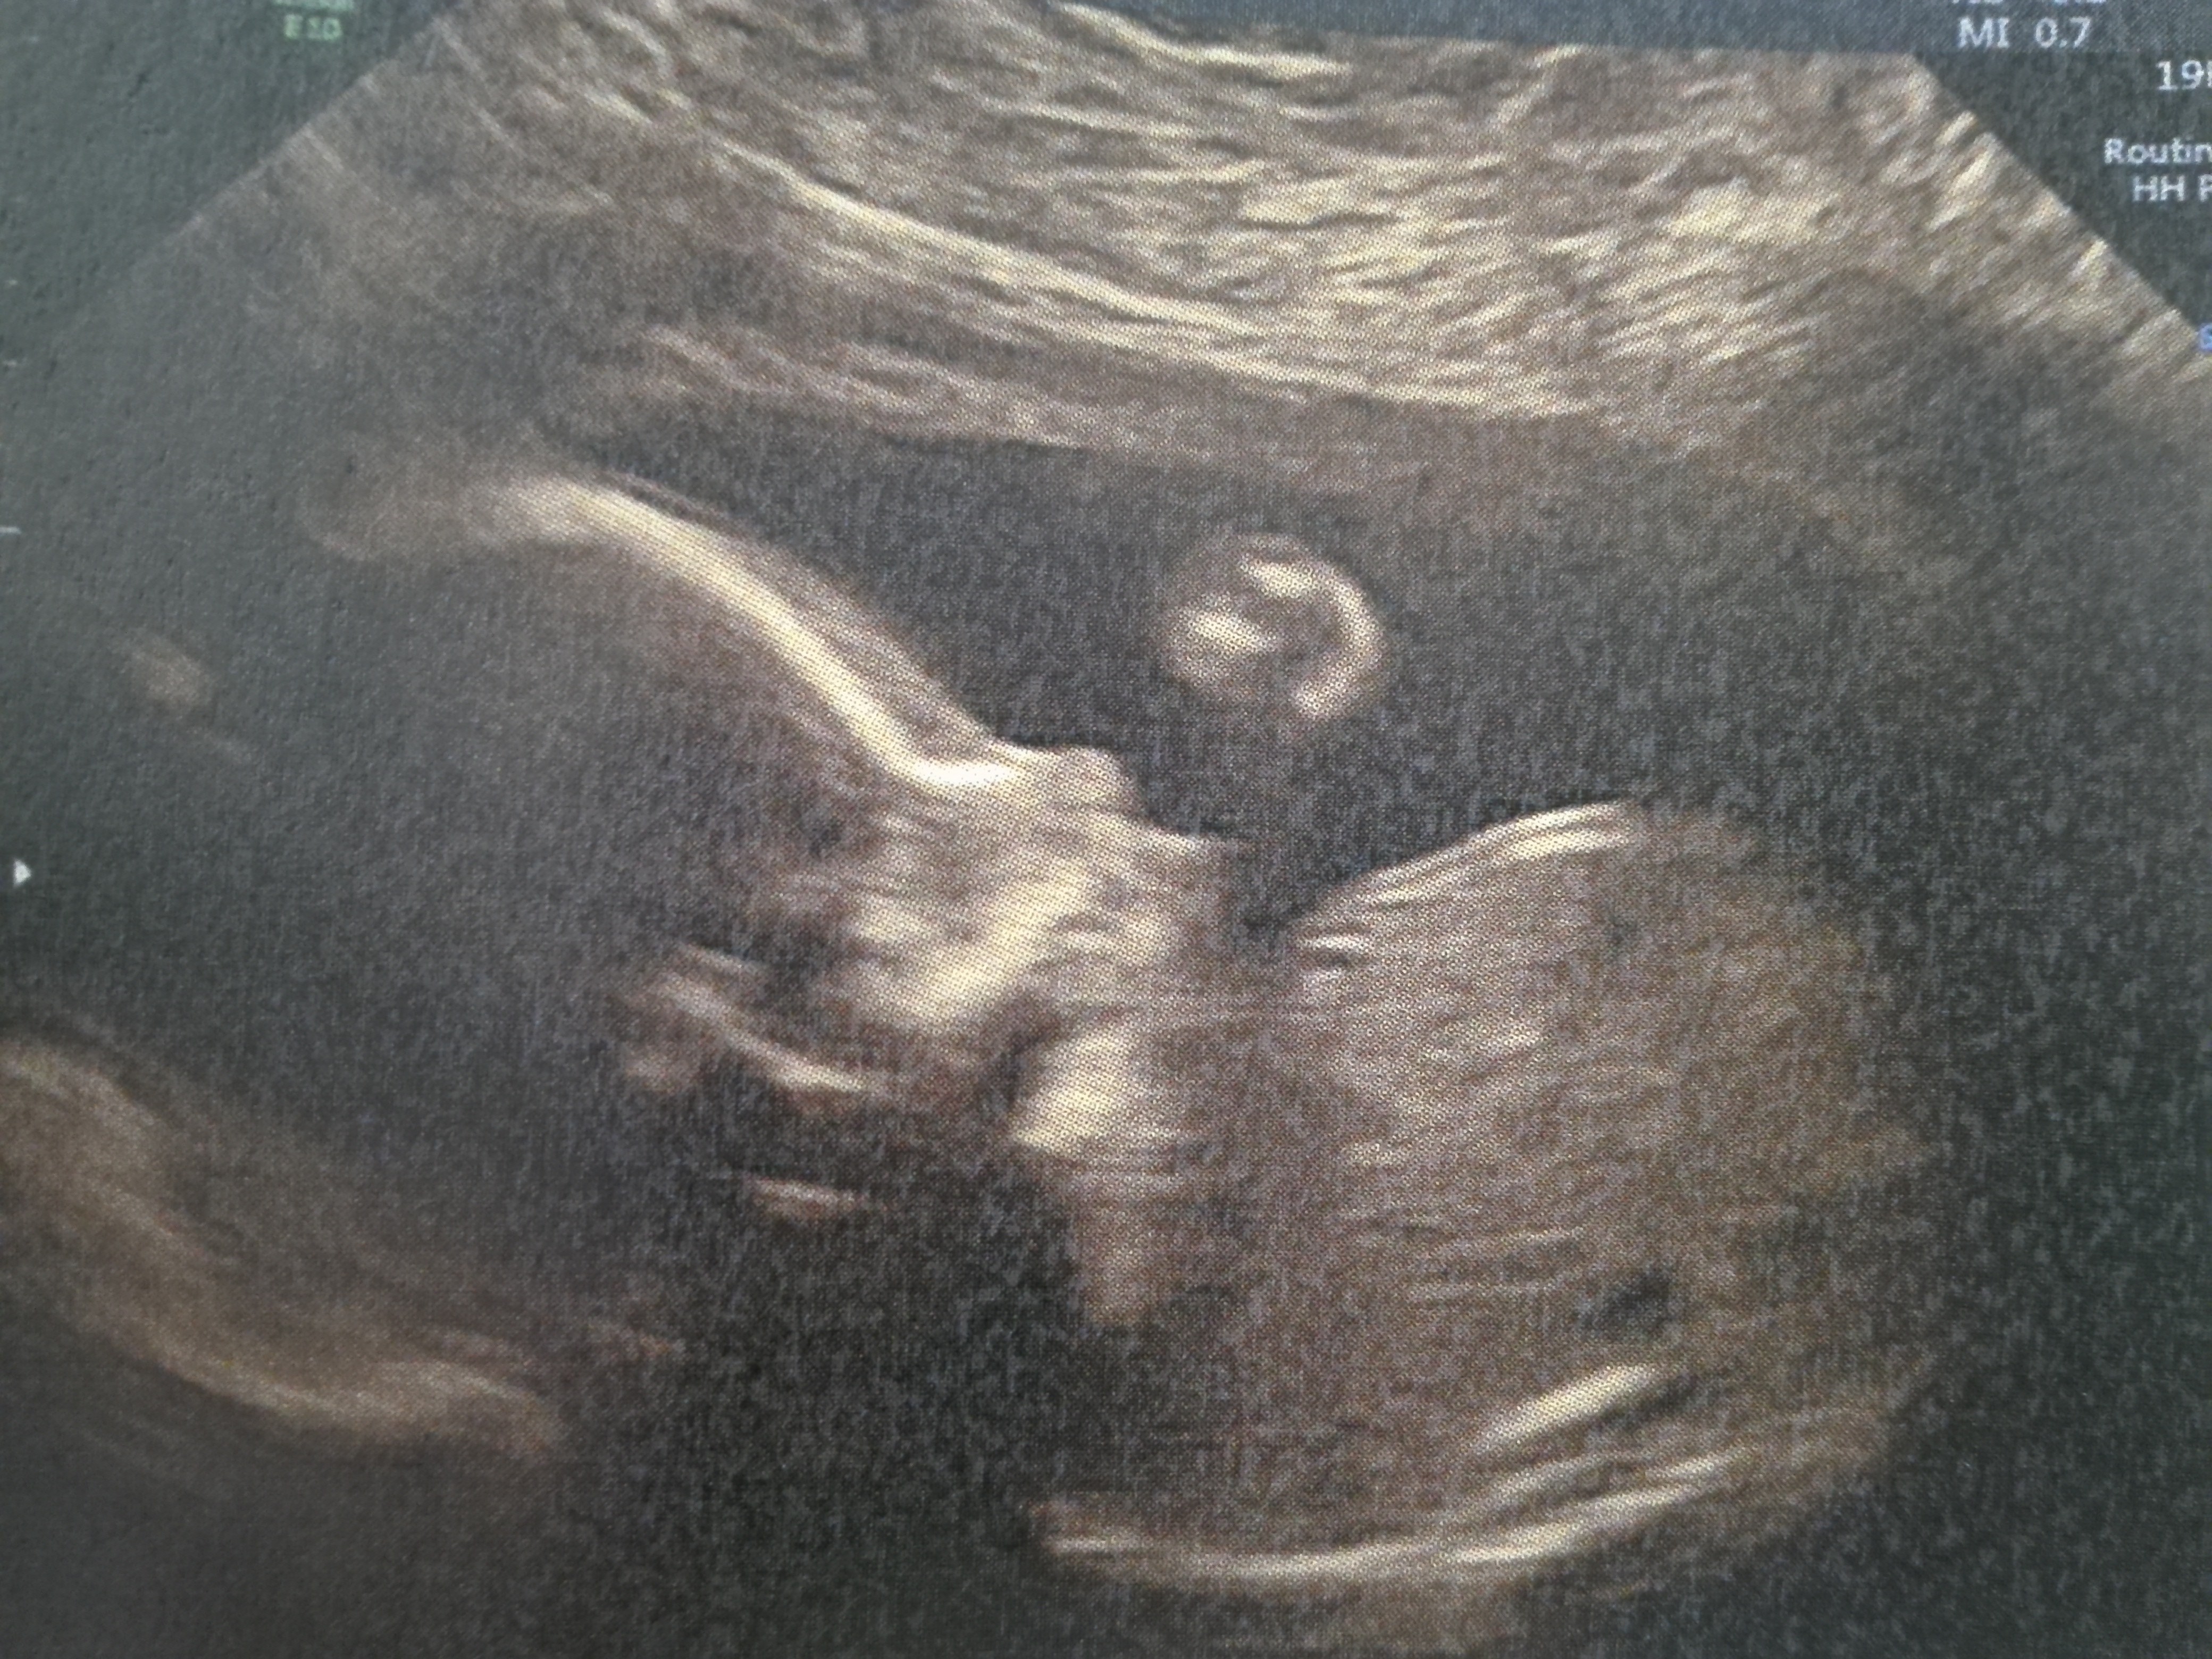

Połówkowe - wyniki

22+2

Dziewczynka

Termin 2 kwiecien

Waga 461g

dlugosc 25 cm

Dziewczynka najwazniejsze, ze zdrooowa <3